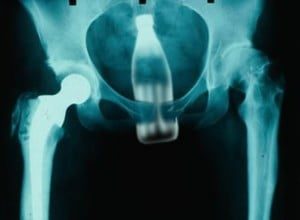

- Cuerpos rectales extraños: informe de casos y una revisión exhaustiva de la literatura mundial (1986); D. Busch y Starling J.

Bombillas, linternas, frutas y hortalizas, botellas…